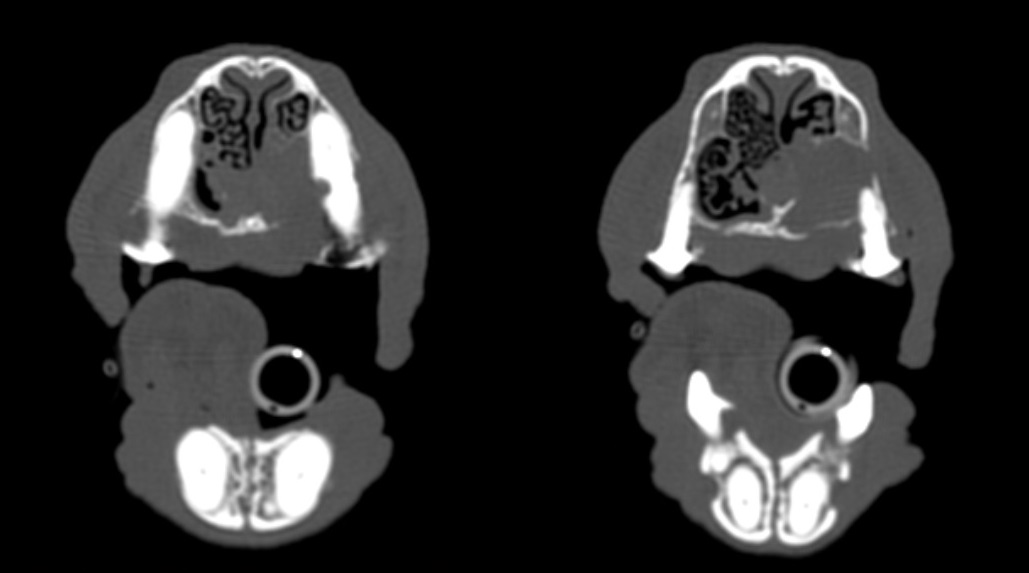

De même, la perte d’os autour des canines et prémolaires peut provoquer une communication oro-nasale (la zone la plus classiquement touchée est la face palatine des canines chez les petits chiens à museau long et fin : Teckel, Caniche…). La gestion de ces communications oro-nasales d’origine parodontale nécessitent les extractions des dents atteintes, le curetage des alvéoles dentaires, de la cavité nasale et la fermeture des sites par de grands lambeaux muqueux suturés sans tension à la muqueuse palatine 9. Les dégâts osseux et nasaux sont préalablement évalués par la réalisation d’un scanner (ou d’un cone beam) afin de visualiser au mieux les structures et planifier l’ampleur des extractions et du curetage (figures 3a à d).

Figure 3b : Scanner du même chien qu’en 3a au niveau de la canine (à gauche) et de la deuxième prémolaire (à droite). Une lyse osseuse péridentaire importante est notable ainsi qu’un envahissement de la cavité nasale D et des structures endonasales.